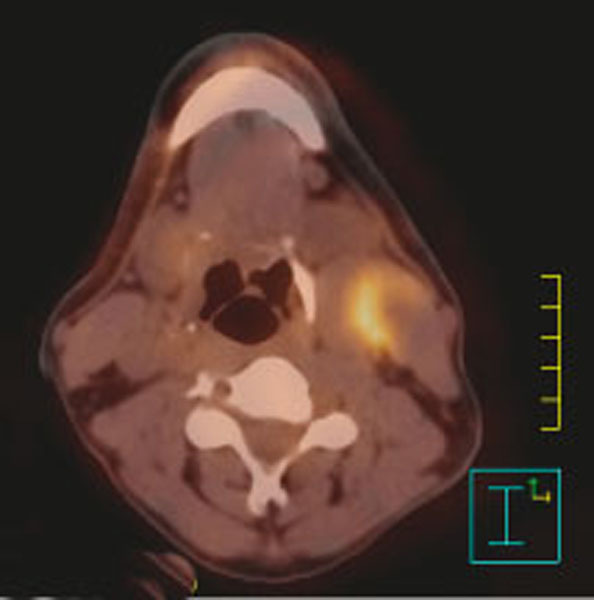

Fixation du fluorodésoxyglucose-(18F) en regard d’un carcinome épidermoïde du sinus piriforme gauche avec une adénopathie tumorale nécrosée sous-digastrique gauche.